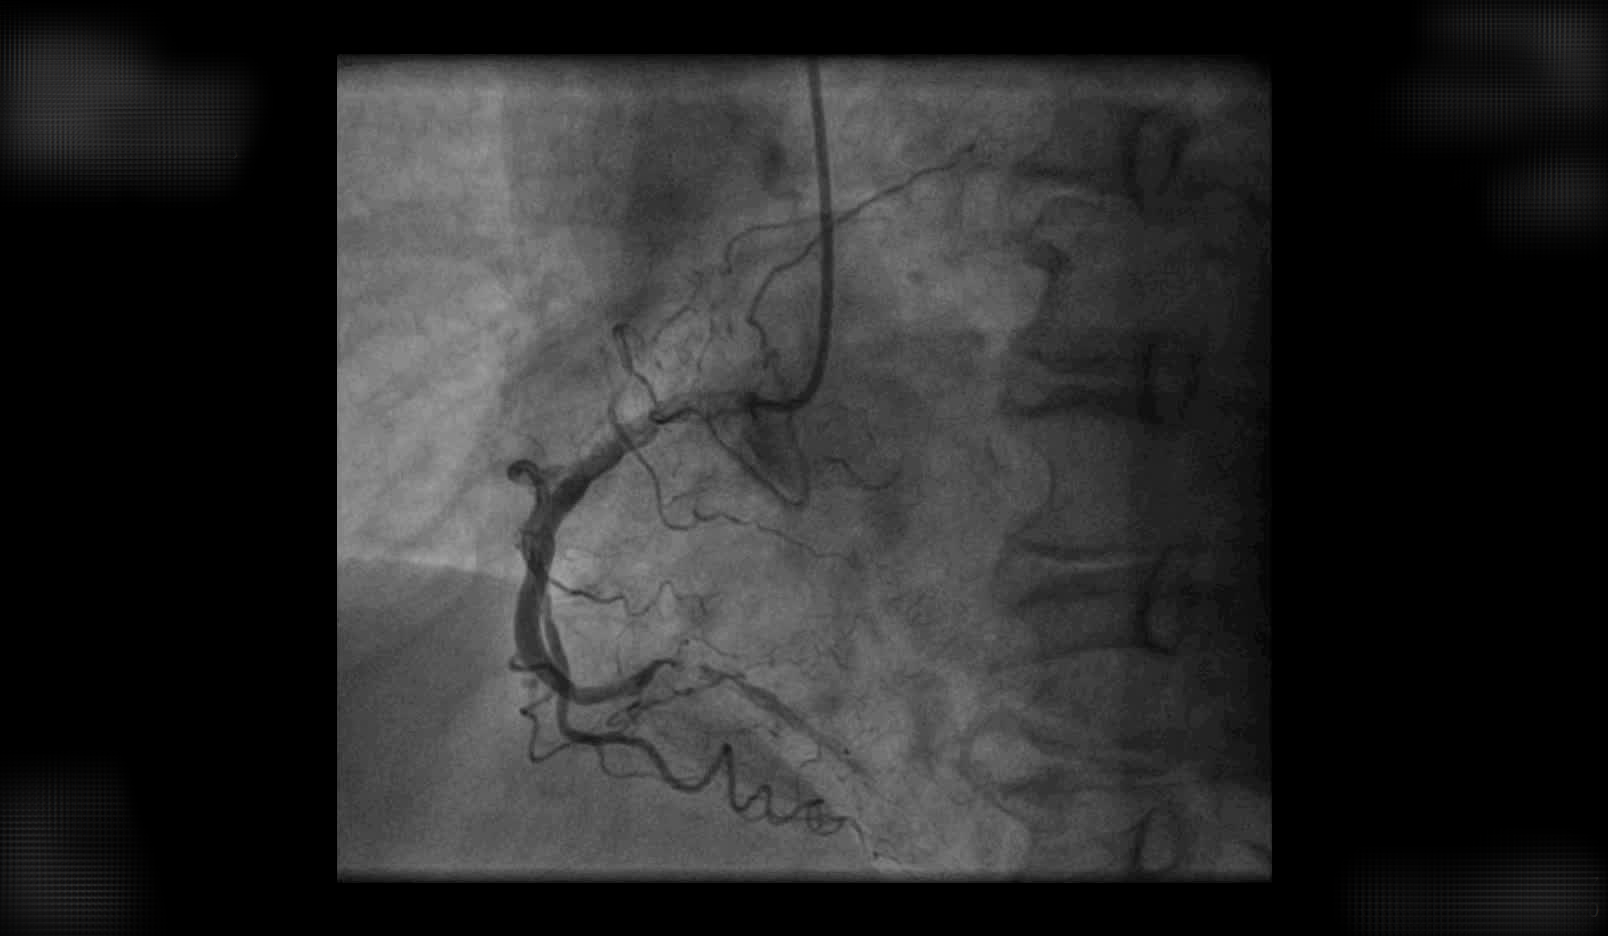

前降支冠状动脉中段100%闭塞 吉心团队选用逆向开通技术,成功为患者开通了闭塞多年的LAD并植入支架。